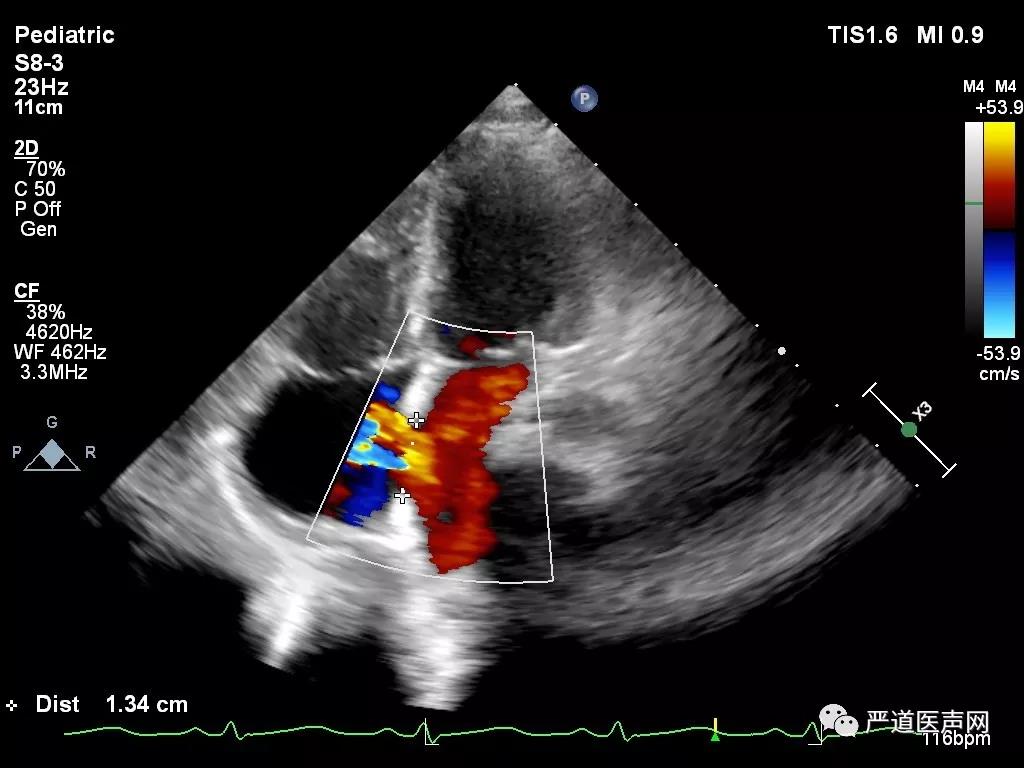

经胸超声心动图提示:右心房增大,房间隔缺损多个切面测量最大直径约12mm(胸骨旁心尖四腔心、大动脉短轴和剑突下四腔心等),患儿具备手术干预指征,选择进行经皮房间隔缺损封堵术,而此次病例的亮点,张智伟教授团队将使用“全球首创”具有自主知识产权的已获中国药监局批准进入临床试验的可吸收房间隔缺损封堵器(Biodegradable ASD closure Device)。

术前超声测量

术中超声显示:房间隔缺损,继发孔型,大小12mm,右心导管检查提示Qp/Qs:1.45,肺动脉压力28/9 (18)mmHg,建立钢丝轨道,选择6F MPA2导管,经房间隔缺损送入左房,置于左上肺静脉,并导入输送钢丝0.035/260cm。